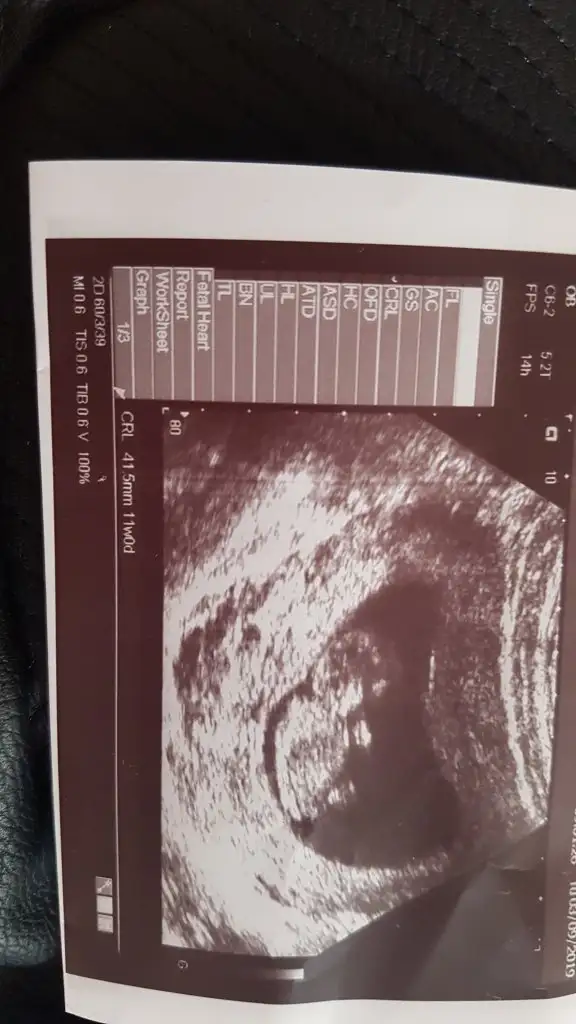

Dr daha iyi goruyor ama bu usg ye gore KizzzMerhaba hanimlar gecen hafta yazmistim nub icin 11 sonrasi daha iyi olur demistiniz bugunde kontrolden geldim cikar mi bi tahmin acaba❤

Erkek